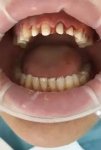

Аноним 20/07/25 Вск 14:44:44 #11 №1632648

Как меня эти мрази заебали. Пришёл полечить кариес зуба, дырочка на верхнем

Все блять, сделали снимок, где нихуя не видно на глаз и все у вас пульпит. Зубу пизда снимки анестезия лечить месяц 4 похода, временная пломба коронка постоянная пломба. 56 тыс рублей давай мразь

Да блять пластиковый вставить 25 тыс стоит

Аноним 22/07/25 Втр 14:40:46 #12 №1632893

Болит вся челюсть с правой стороны, хз, не могу понять, какой именно зуб, будто четыре сразу. Подсвечивание с фонариком не показало никаких видимых отклонений, к стоматологу хожу регулярно, делаю чистки, дома пользуюсь нитью. Жжет в деснах и бывает кольнет где-то в том же районе, как будто током ударило. В интернете пишут про тройничковый нерв, или как там его, вроде похожи симптомы, но как понять, что не в зубах дело? Вдруг они у меня там уже сгнили нахуй, вот и ноют (хотя схуяли им сгнивать, если я два раза в год хожу проверяться)